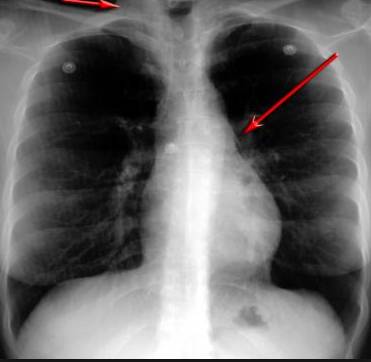

并且,因為呼吸系統結構復雜,在體檢時醫生很難通過一種檢測手段,判定早期患者的病情。

把整個肺部看得清清楚楚!

使用這臺掃描儀,將直接把器官變成3D圖形!細微的毛細血管,幾毫米大的肺泡和支氣管,都將能看的一清二楚!

你的每一個氣泡,每一段支氣管,哪兒有病變都清清楚楚的將展示在醫生面前!

也就是說在一切都還沒開始惡化前,把這些有問題的器官組織都暴露的一清二楚:

不同于CT掃描,需要從同一角度,拍下無數張器官二維圖,從而搭建3D器官結構圖那般費時費力。

4D掃描儀將直接從不同角度,同時對人體器官進行掃描,然后通過計算機算法進行快速成像。CT需要花幾小時才能完成的工作,

4D掃描將在幾秒內完成!

沒有這項新技術,醫生在做體檢的時候,很難通過一種測試斷定一個人是否有呼吸系統疾病。

可是現在他們不但能看到整個肺部的3維結構圖。還能看到空氣進入人體后的所有微小變動!